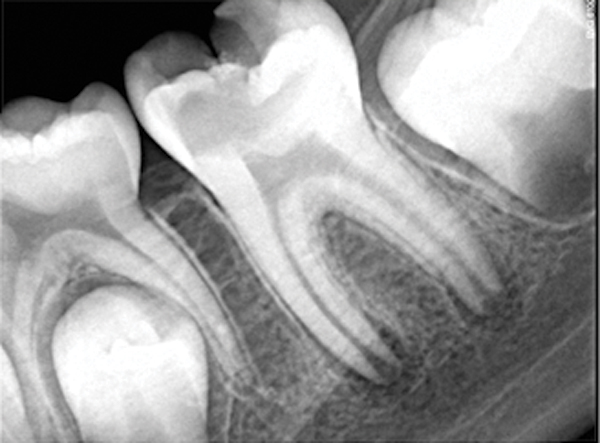

Figure 6. Preoperative radiograph of carious exposure on tooth No. 19. Courtesy of Dr. Mohammed A. Alharbi.

Figure 6

Figure 7. Preoperative pulp exposure after caries removal. Courtesy of Dr. Mohammed A. Alharbi.

Figure 7